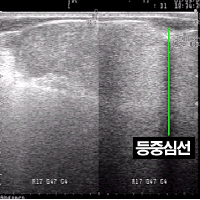

초음파 화상에서 등 중심선은 극돌기의 중심부분에 대한 반사파를 얻지 못하여 검게 나타나므로 비교적 쉽게 알 수 있다(그림 15). 등심의 오른쪽(배다열근 부분) 경계를 나타내는 부위에서 반사파가 좌우 대칭되는 중심의 검은 부분이 등 중심선이다. 등 중심선이 화면에 많이 들어가면 등심 좌측 경계(장늑근 부위)의 작도가 곤란하므로 특히 등심단면적이 클 경우 등 중심선은 화면에서 약간 비칠 정도만 측정하여야 한다.

<그림 15> 등 중심선의 화상